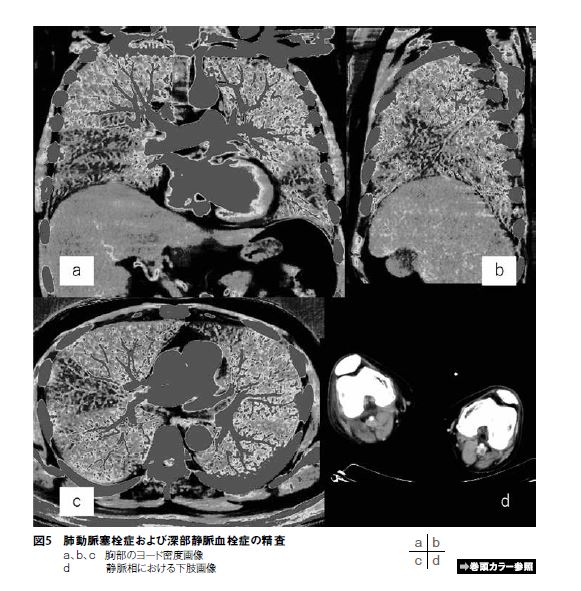

まず、多くの施設が行っている肺動脈塞栓症および深部静脈血栓症の精査について当院の運用を紹介する。造影剤を注入開始後約12秒より肺動脈部に関心領域を置きモニターを始める。造影剤到達後すぐに息止めを行う。なおこの息止めだが、バルサルバ効果により肺動脈の造影効果が下がることを防ぐため安静時息止めを行っている⁵)。造影開始から4分30秒後に下肢静脈の撮影を行う。提出画像について胸部の早期相では、ヨード密度画像を3方向作成しカラー表示にして提供している(図5a、b、c)。GE社ではこのヨード密度画像を“Iodine(Water)” と表現し、ノイズやアーチファクトの少ない画像が提供できる。次に、下肢静脈の評価は造影効果が悪いため、多くの施設で100kVで撮影されている。当院ではGSIを用い40keVの仮想単色X線画像を提供している。このことで造影不良で評価困難となることが少なくなり下肢静脈血栓の評価が容易となる(図5d)。